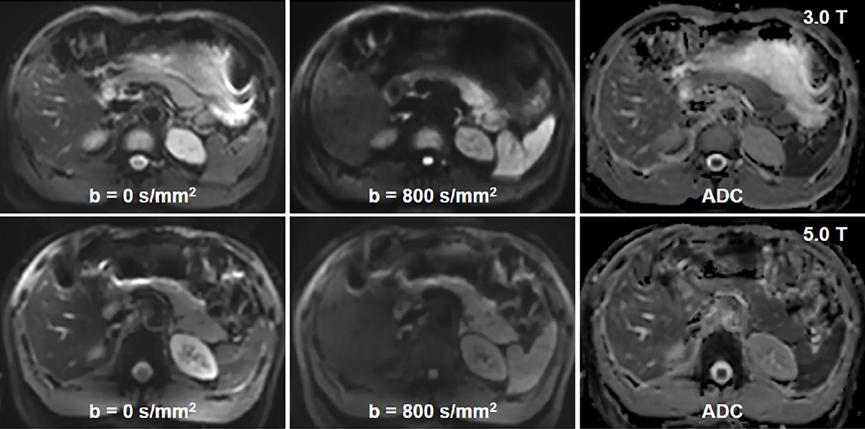

图1. 3.0T 和 5.0T 弥散成像代表性案例

研究共纳入 9 名志愿者,基于联影 3.0T 磁共振 uMR 780 和 5.0T 磁共振 uMR Jupiter,志愿者分别接受 3.0T 及5.0T 腹部 DWI 检查(b=0 s/mm2 和 800 s/mm2),基于单指数弥散模型计算出 ADC 功能参数图,由两位资深腹部影像专家在对扫描参数和患者信息不知情的前提下,分别对肝脏、脾脏、胰腺和肾脏在两种不同场强下的 ADC 进行测量。

使用 Wilcoxon 秩和检验,Bland–Altman 法,组内相关系数(Intraclass Correlation Coefficients, ICC),变异系数(Coefficients of Variation, CV)评估 ADC 场强间一致性和观察者间一致性。此外两位腹部影像专家也对 3.0T 和 5.0T DWI 的主观图像质量进行评分(最低1.0 分,最高5.0 分)。研究结果表明,5.0T DWI 的图像质量评分高于 3.0T DWI (5.0T: 3.72±0.42,3.0 T: 3.50±0.47)。